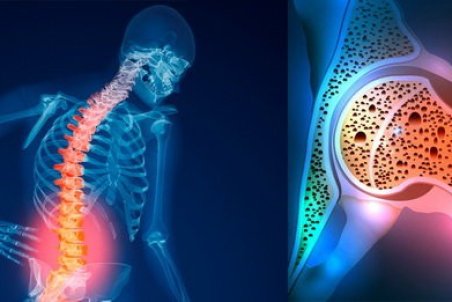

یکی از علل مهم مرگ و میر در سراسر دنیا پوکی استخوان است. استخوان بافت زندهای است که مدام در حال تخریب و بازسازی است اما معمولا از سن 35 تا 40 سالگی به بعد جذب کلسیم کم شده و به علت برداشت کلسیم از استخوان، پوکی استخوان شروع میشود و به دنبال آن افزایش احتمال

قدرت استخوانهای بدن ما را ۲ عامل اصلی تراکم استخوان و کیفیت استخوان تعیین میکند. پوکی استخوان یک بیماری عمومی استخوان است که با توده استخوانی پایین و تخریب زیرساخت بافت استخوانی و متعاقبا افزایش شکنندگی و مستعد شدن به شکستگی همراه است. تشخیص پوکی استخوان با

دردی خاموش به نام "آستئوپروز"

بیماری پوکی استخوان یا «آستئوپروز» معروف به درد خاموش، عارضهای است که در آن، تراکم سلولهای استخوانی کم و از قدرت طبیعی آن کاسته میشود و در این حالت استخوان شکننده خواهد شد و احتمال شکستگی حتی بر اثر ضربات کوچک افزایش مییابد.